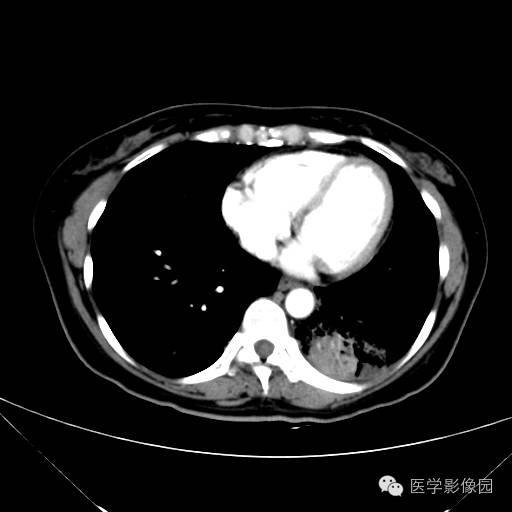

肺叶实变性支气管肺泡癌1例CT影像表现